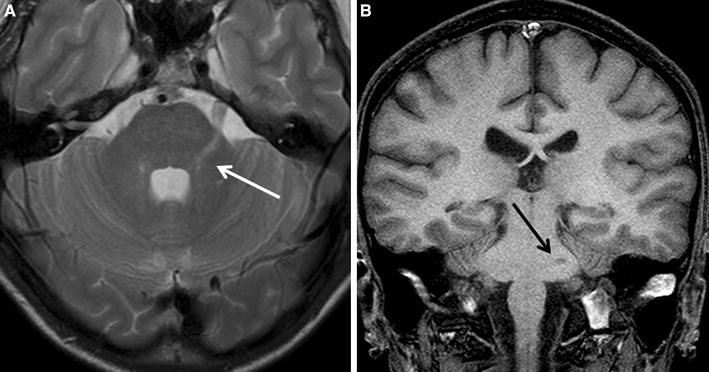

Neuroimage studies